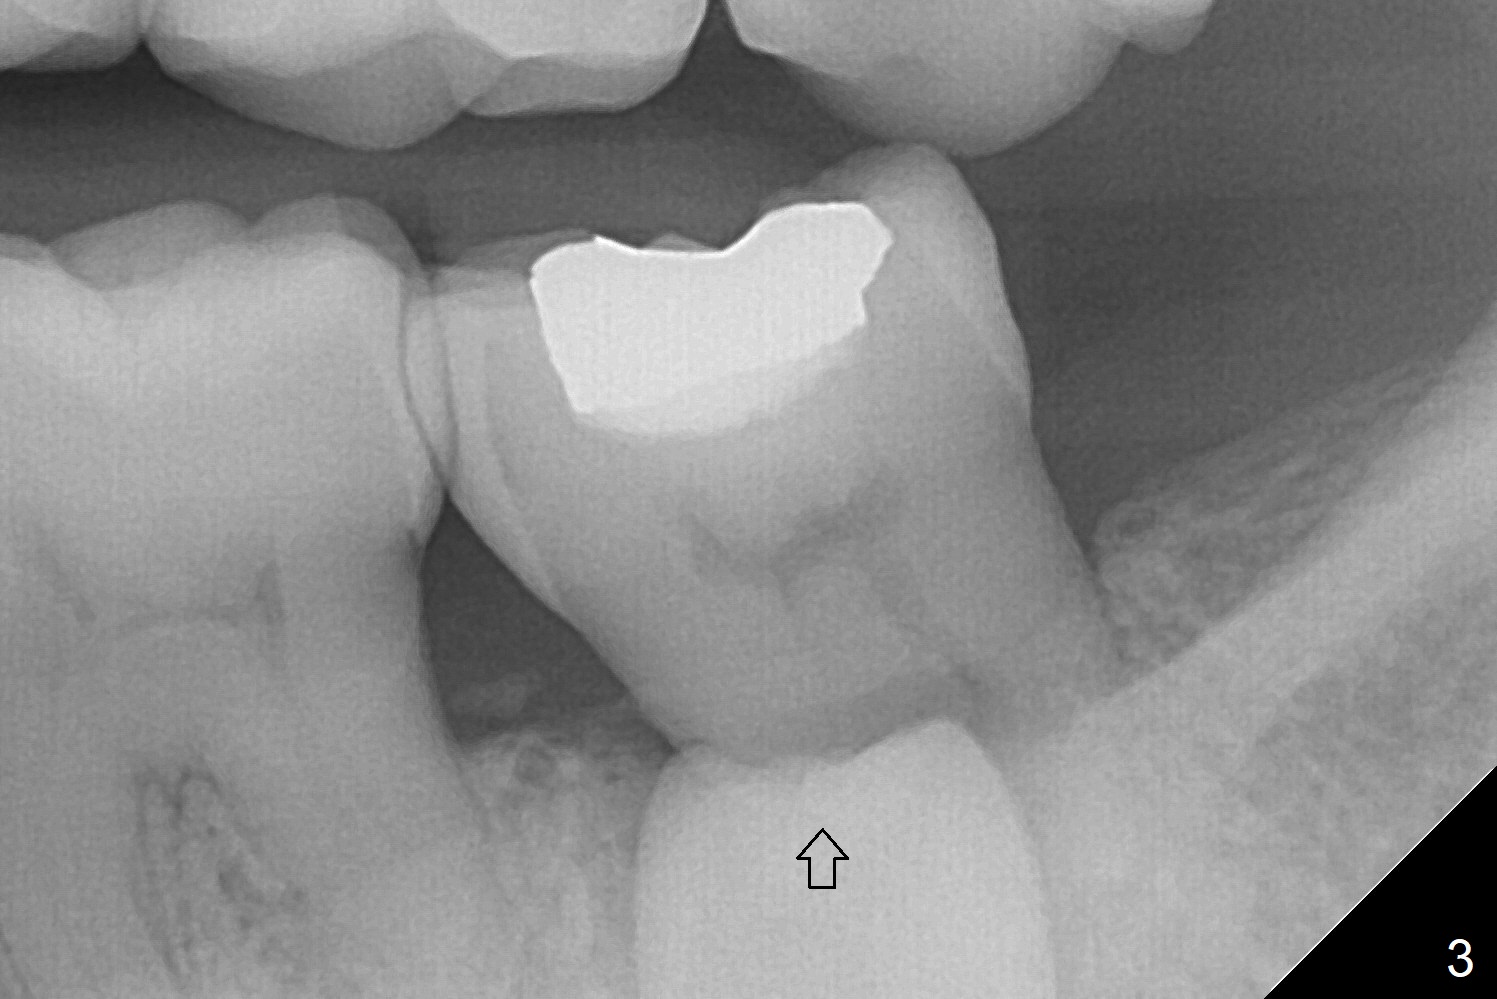

A 45-year-old woman with severe crowding (Fig.2) presented to my office 9 years ago; the tooth #18 appears to have root resorption, most likely due to a supernumerary tooth (Fig.1 *). The latter seems to be erupting in 6 and 9 years (Fig.2,3), probably because of immature apex (Fig.2, as compared to the supernumerary tooth in the lower right (*)). Recently the patient has transient sensitivity at #18. The tooth has mobility I without deep periodontal pockets. If the tooth #18 turns to be non-salvageable, what should be done? The tooth #20 has received root canal therapy, while the tooth #29 has had RCT retreat.

Reply: Thanks. Since the supernumerary tooth seems to have open apex with

potential to erupt, the maxillary molars will be used anchorage after initiation

of ortho (for crowding). With lingual button(s) to be placed on the

supernumerary tooth while the tooth #18 is extracted and elastics between the

upper molars and lingual buttons, the extra tooth may be able to erupt into the

site of #18. If not, extraction and implant. Ortho may involve extraction U4s

and L5s.